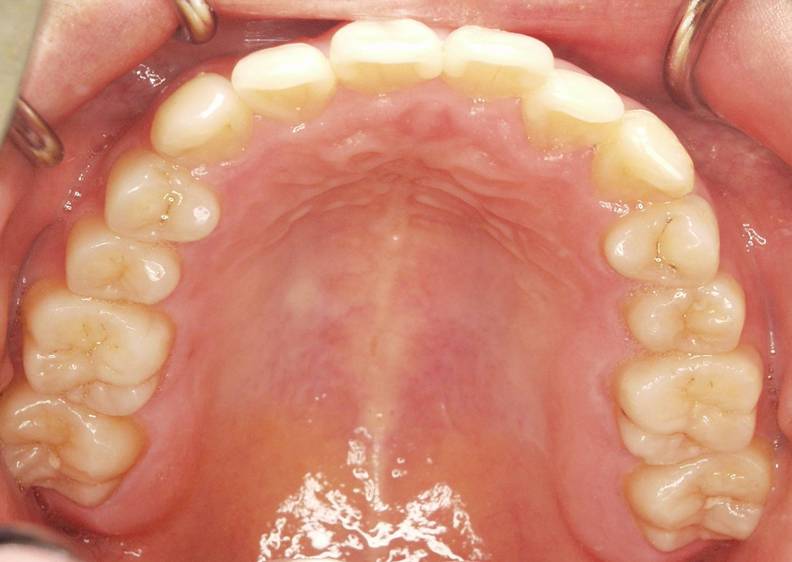

次の写真はすり減っていない健康な歯です。

こちらも同じように歯の本数がしっかりあります。

健康な歯はこの方のように山谷がしっかりあり歯の頭もすり減っていません。